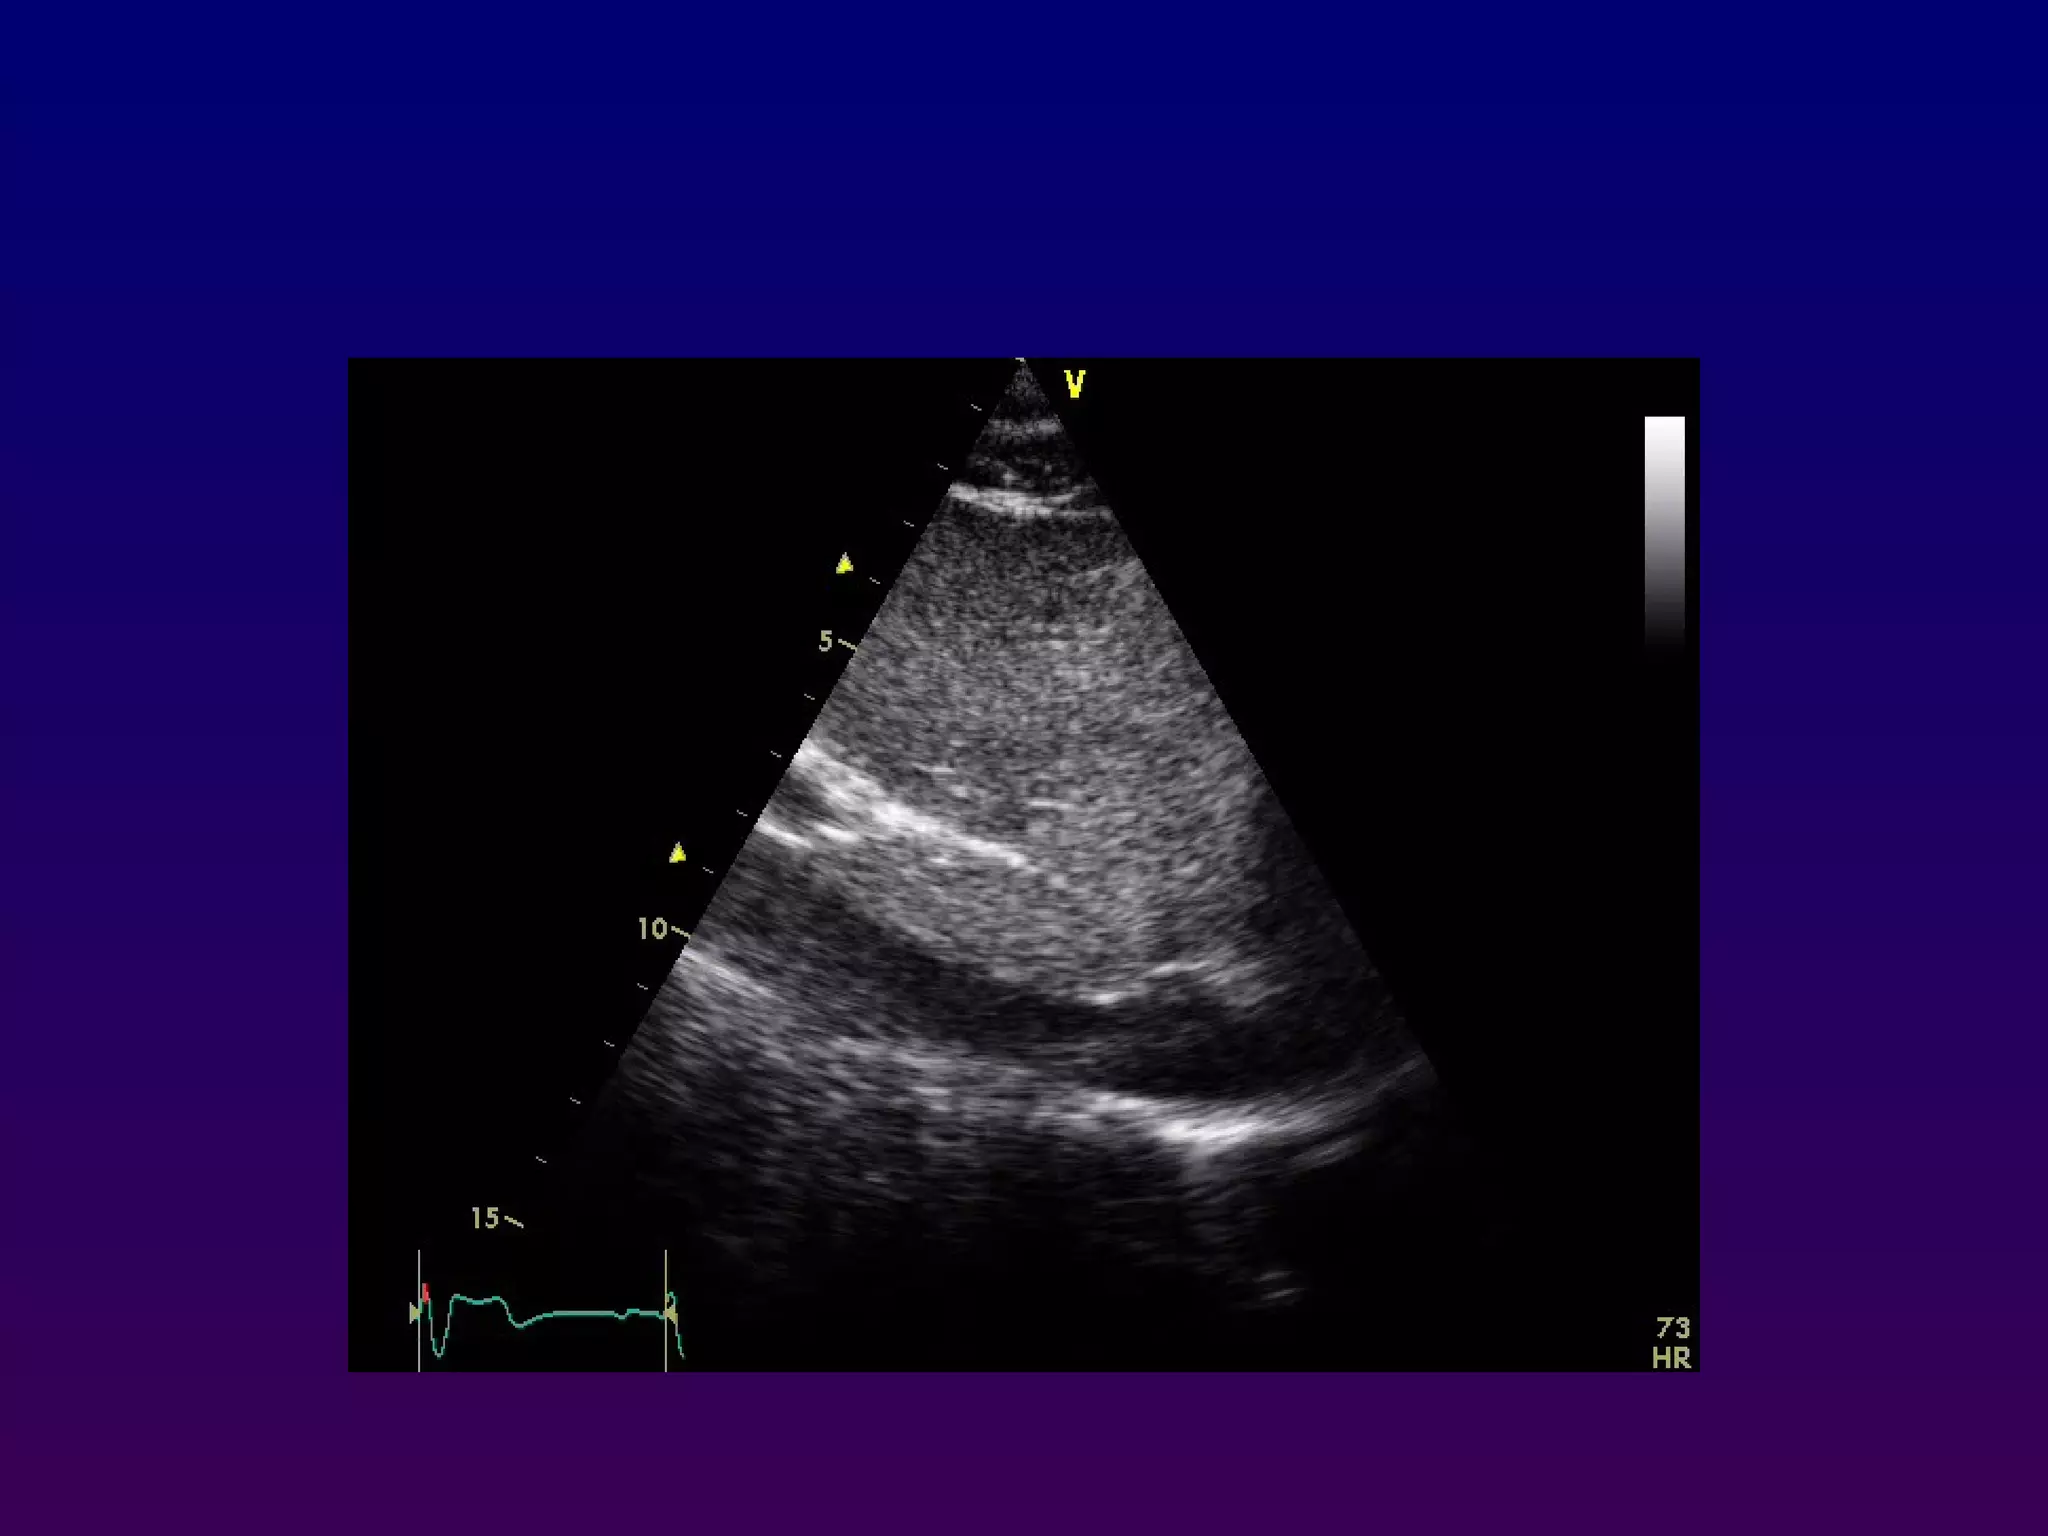

In the apical four-chamber view, all four

chambers of the heart may be seen The left

ventricle appears as a truncated ellipse,RV

triangular with the interventricular septum, apex

formed by LV, and lateral walls visualized.

With the patientmaintained in the left lateral decubitus position, the transducer is placed near the apex of the heart with an inferior orientation In the apical four-chamber view, all four chambers of the heart may be seen The left ventricle appears as a truncated ellipse,RV triangular with the interventricular septum, apex formed by LV, and lateral walls visualized. Apical four-chamber